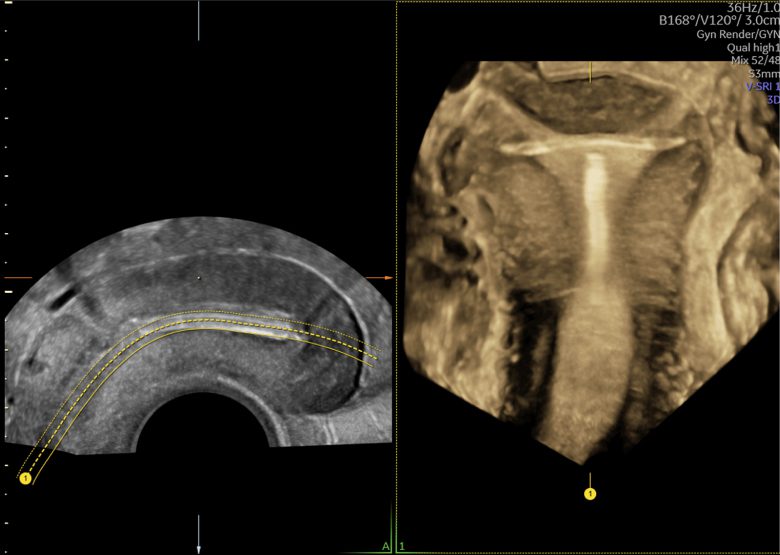

Imagens clínicas

Imagens 2D e 3D/4D de próximo nível

Imagens clínicas

Imagens 2D e 3D/4D de próximo nível